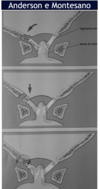

Fratura do processo odontoide

Tipo III de Anderson e D’alonzo.

Envolve o corpo de C2.

Estável, melhor prognóstico;